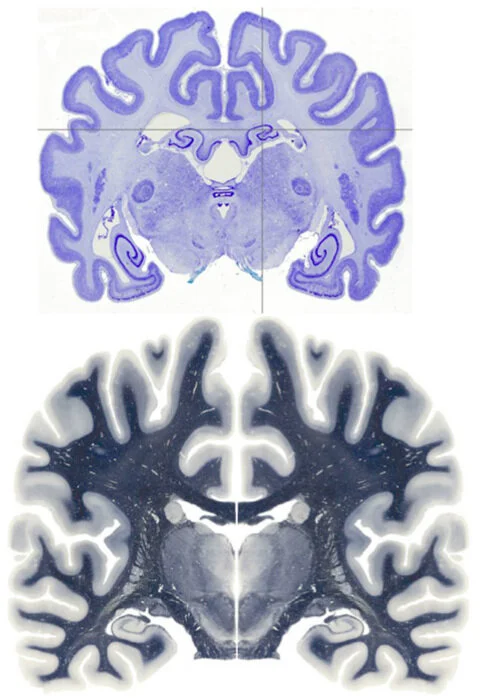

The canine brain (image upper) is a beautiful thing. The dog’s thinking neocortex is remarkably similar to the human brain (image lower), layered with hills and valleys (gyri and sulci) that rodents just don’t have (the rodent brain is smooth).

The canine brain’s hippocampus (memory centre) is also remarkable - it has a dorsal (upper) part very much like the rodent hippocampus (denoted by the crosshairs), and a ventral (lower) part very much like the human hippocampus.

So the canine brain really is a bridge between rodents and humans, and that is what has been missing in Alzheimer and dementia research for so long.